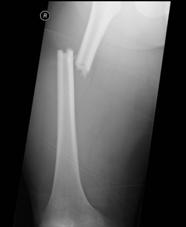

TRAUMA CERVICALA

Incidenta laterala Incidenta

laterala Incidenta

antero-posterioara

Aspect normal Imagine

incompleta Aspect

normal

Incidenta occipitomentala (odontoida)

Aspect normal Incidenta

oblica

Aspect normal

Incidenta oblica Incidenta laterala Incidenta antero-posterioara

Aspect normal Aspect normal Aspect normal